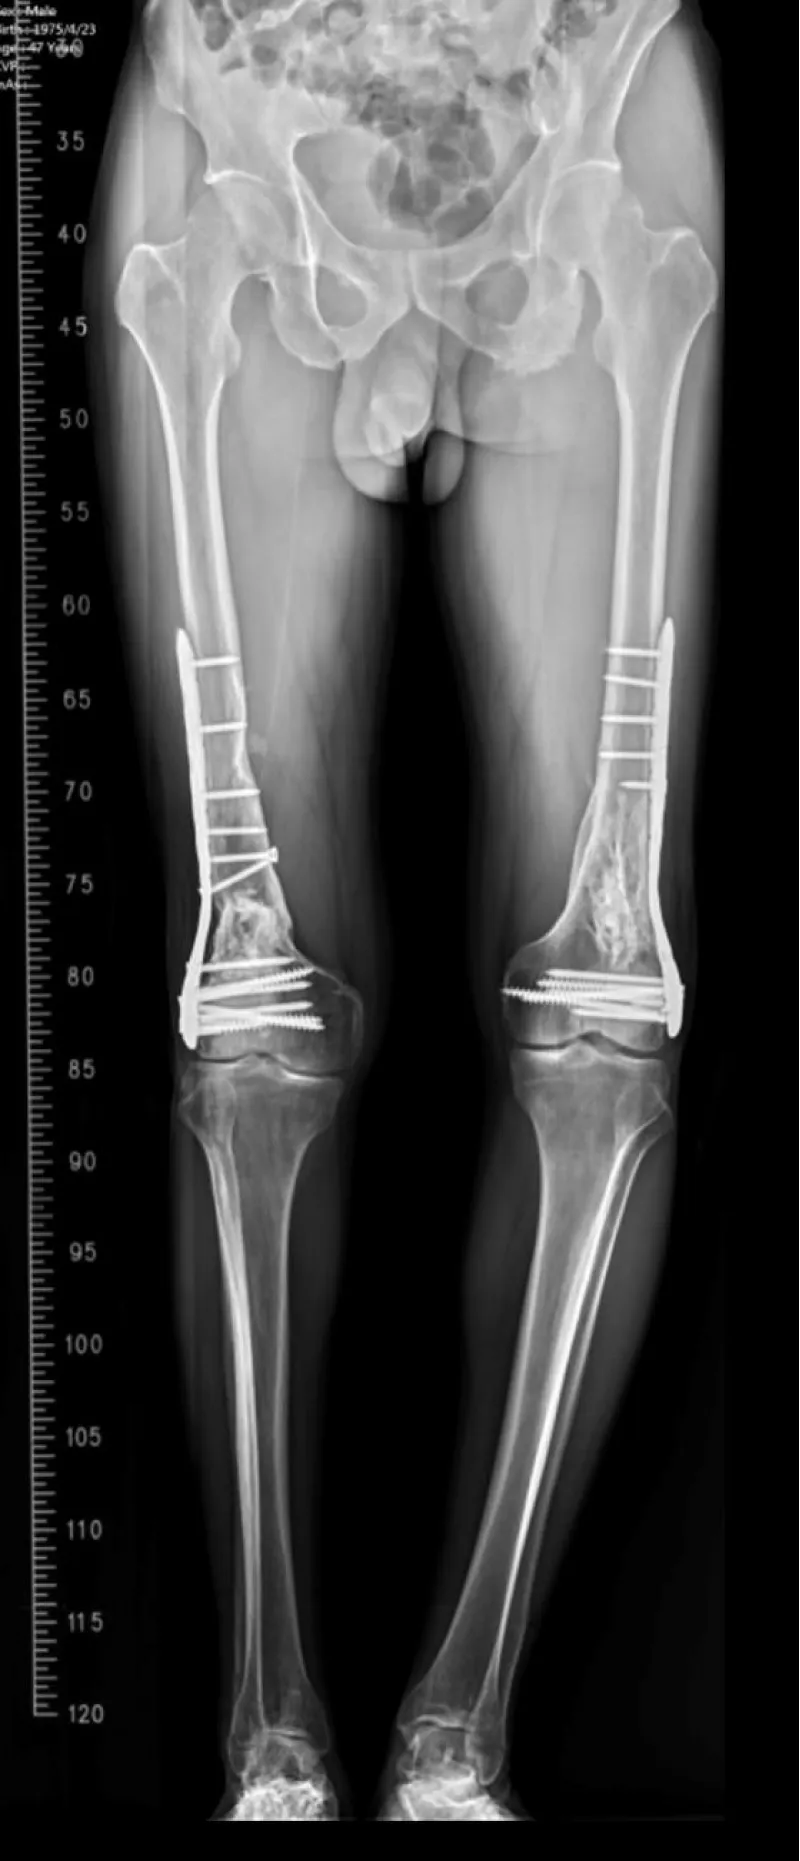

Figure 4: Long-leg standing follow-up radiograph confirming alignment and interval bony consolidation after staged ORIF.

At outpatient follow-up, the patient ambulated independently without exertional dyspnea. On examination, the bilateral knee range of motion measured 2°–110° with no extensor lag. Radiographs demonstrated progressive callus with maintained alignment; no readmissions or supplemental oxygen were required.